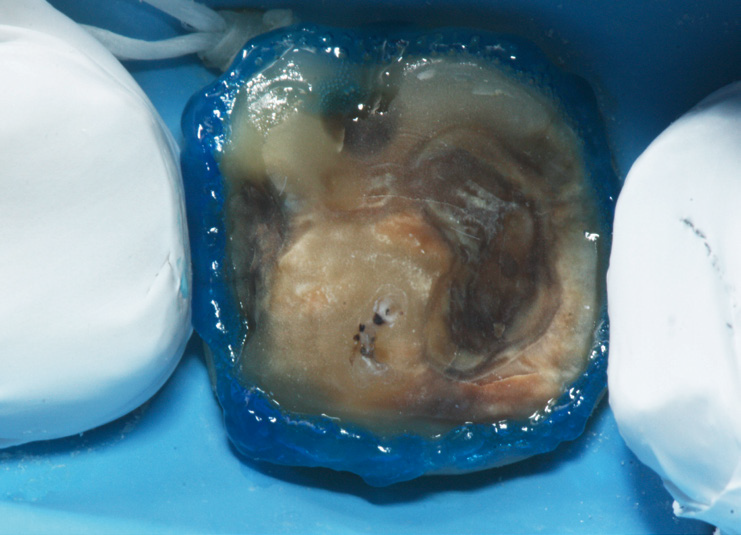

A close-up of a decayed tooth, isolated with blue dental dam material, showing significant discoloration and cavity damage.

Selective enamel etch with 3M™ Scotchbond™ Etchant after cleaning of prep with 50 μm alumina.